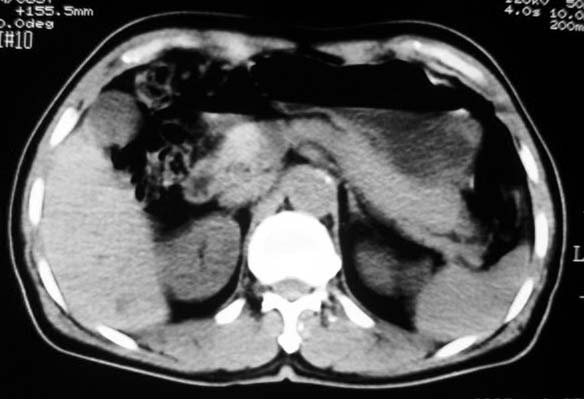

胃底与体交界侧壁一息肉样改变,以宽基与胃壁相连且胃壁僵硬,考虑胃恶性病变(胃癌?息肉恶变?)伴脾门淋巴结肿大可能性大。

定位:病灶位于胃腔外,大弯侧后下方.

特征:实质性肿物,边界清楚,内见低密度影,明显压迫胃壁,并形成切迹.

胃大弯侧,胃底与胃体交界处可见一圆形软组织肿块影,边缘较光整,内部密度较均匀

病灶起源于胃壁向腔内外突出,边缘光整,内可见片状低密度区,考虑胃壁非上皮性肿瘤可能性大

病灶起源于胃壁向腔内外突出,边缘光整,内可见片状低密度区,考虑间质瘤可能性大,建议增强扫描。